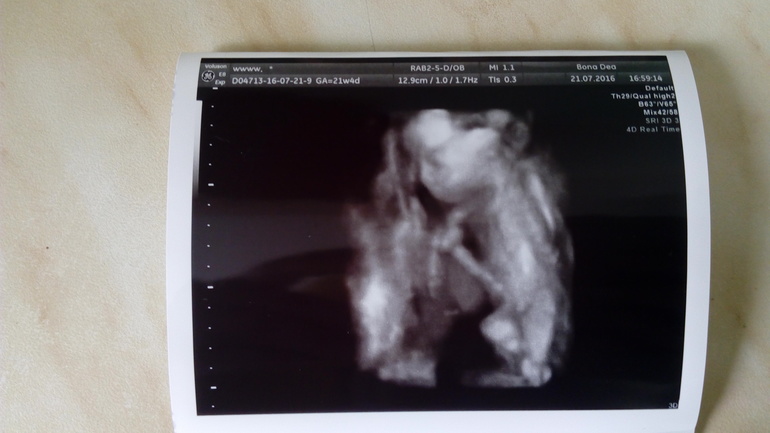

А сегодня была на 3d узи:) Подтвердили нам девочку!! Весит уже 560 гр (2 недели назад была 330гр). Сказали поменьше сладкого, а то быстро вес набирает. Из 25 минут узи 95% времени спала с пальцем во рту, зевала и руки под голову))) Пуповина на 90% в ножках лежит (врач сказала очень хорошо, маловероятно обвитие в дальнейшем).